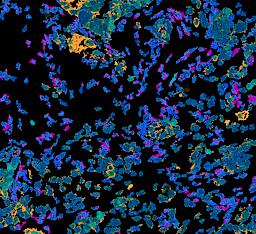

Pancreatic ductal adenocarcinoma is a lethal disease with limited treatment options and poor survival. We studied 83 spatial samples from 31 patients (11 treatment-naïve and 20 treated) using single-cell/nucleus RNA sequencing, bulk-proteogenomics, spatial transcriptomics and cellular imaging. Subpopulations of tumor cells exhibited signatures of proliferation, KRAS signaling, cell stress and epithelial-to-mesenchymal transition. Mapping mutations and copy number events distinguished tumor populations from normal and transitional cells, including acinar-to-ductal metaplasia and pancreatic intraepithelial neoplasia. Pathology-assisted deconvolution of spatial transcriptomic data identified tumor and transitional subpopulations with distinct histological features. We showed coordinated expression of TIGIT in exhausted and regulatory T cells and Nectin in tumor cells. Chemo-resistant samples contain a threefold enrichment of inflammatory cancer-associated fibroblasts that upregulate metallothioneins. Our study reveals a deeper understanding of the intricate substructure of pancreatic ductal adenocarcinoma tumors that could help improve therapy for patients with this disease.